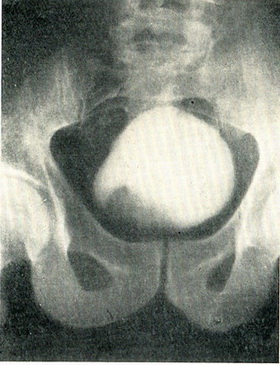

Гістологічне дослідження шматочка пухлини, взятого гострою ложечкою через цистоскоп, дозволяє диференціювати пухлину із грануляційною тканиною, туберкульозом або іншими запальними процесами. За даними біопсії далеко не завжди вдається встановити доброякісність або злоякісність пухлини. При цистографії з 10% розчином сергозина на місці пухлини видно дефект наповнення. Якщо контури міхура залишаються при цьому незмінними, то пухлина з великою ймовірністю можна вважати неинфильтрирующей (рис. 111). Якщо поряд з дефектом наповнення нерівні контури міхура, є асиметрія менаду правою і лівою половиною міхура, то в инфильтрирующем характер пухлини можна не сумніватися (рис. 112).

Рис. 111. Неинфильтрирующая папілярна пухлина сечового міхура, дефект наповнення праворуч. Контури міхура не змінені. Цистограмма з 10% сергозином.